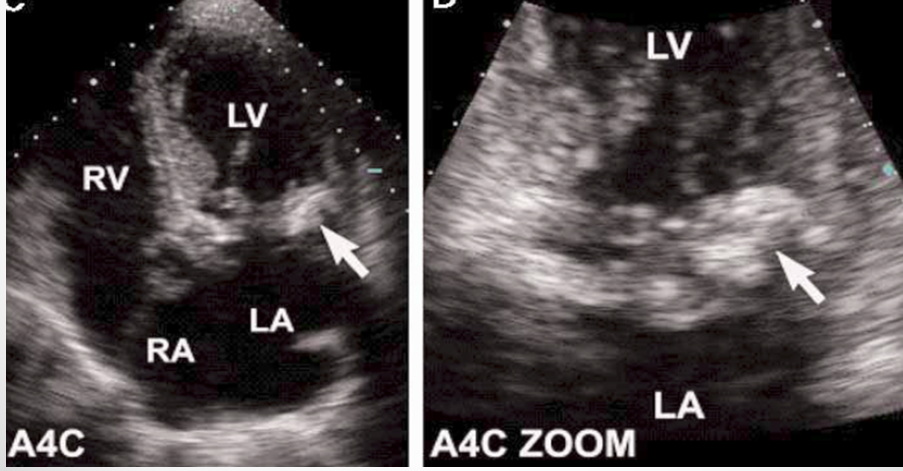

what is seen here?

endocarditis vegetation of tricuspid leaflets and infectious abscess of aortic annulus